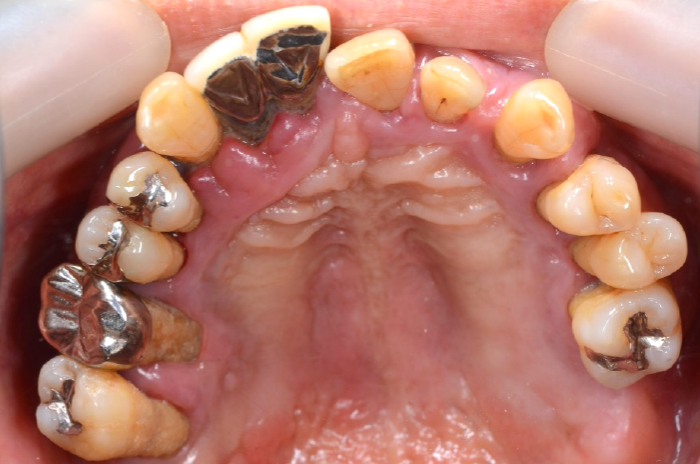

初診時の状態

歯周病により歯はグラグラの状態で、元の位置から動いてしまっていました。

また、レントゲン写真でも歯を支えている骨が吸収していることが明らかで、噛む力を十分に支えられない状態でした。

このままの状態で歯を残すことは難しく、抜歯が必要と判断しました。

初診時口腔内写真